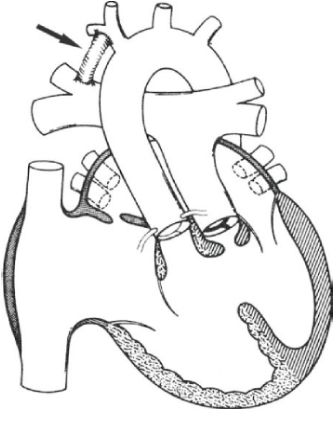

При ТМС с ДМЖП операция артериального переключения выполняется совместно с закрытием дефекта межжелудочковой перегородки. Если также присутствует обструкция выводного тракта левого желудочка, то зачастую анатомическая коррекция выполняется в два этапа: сначала создаётся системно-лёгочный анастомоз (соединение) между аортой и лёгочной артерией, чтобы увеличить количество крови в малом кругу кровообращения и повысить сатурацию. При наличии стеноза выносящего отдела левого желудочка клапан лёгочной артерии не подходит для артериального переключения и будущей работы в роли системного клапана. Поэтому вторым этапом выполняется анатомическая коррекция — операция Растелли, REV или Никайдо.

![Схематическое изображение сердца с ТМС, ДМЖП и обструкцией ВТЛЖ после операции создания системно-лёгочного анастомоза. Анастомоз между безымянной артерией и правой ветвью лёгочной артерии обозначен стрелкой [2] Схематическое изображение сердца с ТМС, ДМЖП и обструкцией ВТЛЖ после операции создания системно-лёгочного анастомоза. Анастомоз между безымянной артерией и правой ветвью лёгочной артерии обозначен стрелкой [2]](/media/bolezny/transpoziciya-magistralnyh-sosudov/shematicheskoe-izobrazhenie-serdca-s-tms-dmzhp-i-obstrukciyay-vtlzh-posle-operacii-sozdaniya-sistemno-lyogochnogo-anastomoza-anastomoz-mezhdu-bezymyannoy-arteriyay-i-pravoy-vetvyu-lyogochnoy-arterii-oboznachen-strelkoy-2_s.jpeg)

Схематическое изображение сердца с ТМС, ДМЖП и обструкцией ВТЛЖ после операции создания системно-лёгочного анастомоза. Анастомоз между безымянной артерией и правой ветвью лёгочной артерии обозначен стрелкой [2]